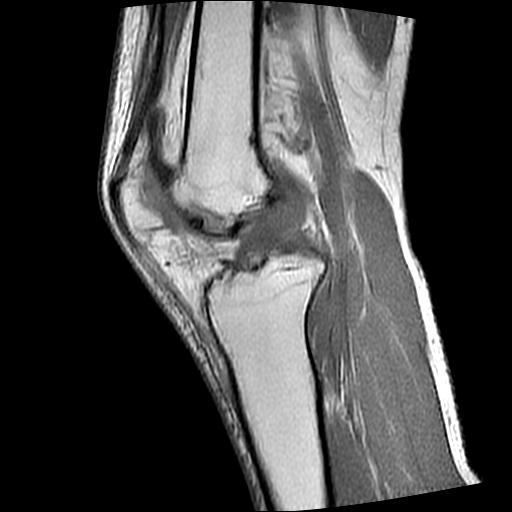

标题: MRI1265:男性40岁,右膝关节 [打印本页]

标题: MRI1265:男性40岁,右膝关节

40岁男性,右膝关节外伤,x光平片示,髁间隆突撕脱骨折。

1、前交叉韧带撕裂;

2、外侧半月板后角撕裂;

3、关节腔积液。

前交叉韧带撕裂,关节腔积液.

半月板1-2级损伤   前交叉韧带撕裂伤   关节腔少量积液  诸骨未见新鲜外伤性改变

髁间隆突撕脱骨折;内侧副韧带损伤。

内侧副韧带撕裂及关节腔积液是肯定的,但是前交叉撕裂确定吗?会不会有容积效应的因素,因为前一张前交叉显示清楚,连续性良好,且较光滑。请问楼主有关节镜支持吗?我们医院也经常有这样的患者,但苦于没有关节镜,而无法对照、证实(除非完全断裂),出现了不同的诊断结果只能毫无意义的争论。

1、前交叉韧、内侧副韧带撕裂;

3、关节腔积液。4、髁间脊撕脱骨折。

除了关节积液外并无韧带撕裂,acl胫侧附着点有2束,正常情况下脂肪信号。此病例应加做压脂像以便观察是否有骨损伤。